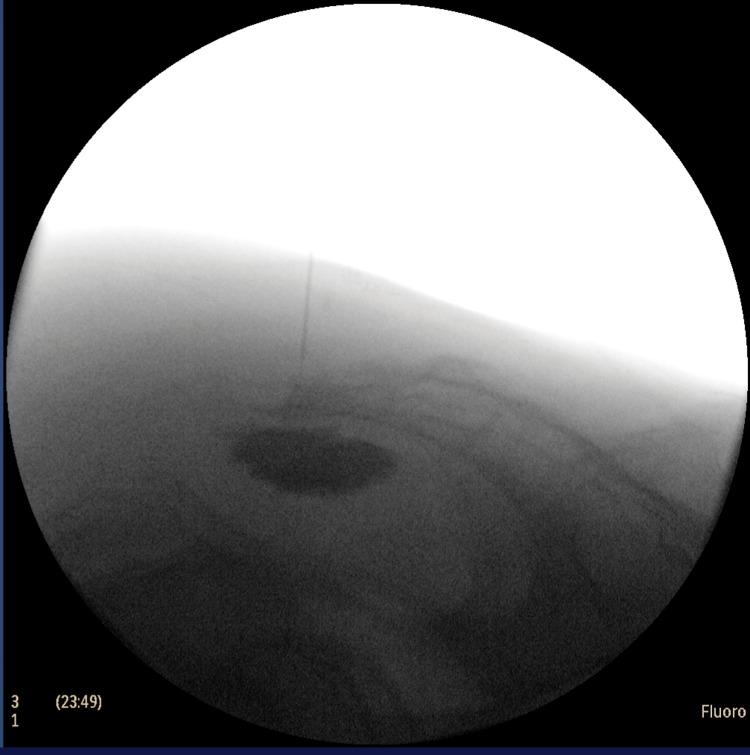

Perineal pain in patients with pelvic malignancies, such as rectal cancer, can be debilitating and significantly impair quality of life. The ganglion impar block (GIB) is an established interventional technique for managing such pain. However, anatomical changes following pelvic radiotherapy, particularly sacrococcygeal fusion, may render conventional approaches to GIB ineffective or unsafe. We report the case of a 41-year-old male with locally advanced rectal cancer and radiation-induced sacrococcygeal fusion who presented with severe, refractory perineal pain. Pain was poorly controlled despite systemic opioids and adjuvant analgesics, and conventional trans-sacrococcygeal GIB attempts under fluoroscopy failed due to the inability to traverse the fused joint. A novel coaxial transosseous technique was employed. A large-bore (21G) needle was used in a rotatory fashion to drill through the ossified sacrococcygeal joint. Subsequently, a 27G spinal needle was introduced coaxially through the first needle, facilitating precise placement and administration of therapeutic agents under fluoroscopic guidance. The patient reported significant and sustained pain relief. Post-procedure, the patient experienced substantial pain reduction (Numerical Rating Scale 8/10 to 2/10), improved defecation-related symptoms, and enhanced functional status. No procedural complications were observed. Follow-up at one week confirmed ongoing analgesic benefit with reduced opioid requirements. The coaxial transosseous GIB is a safe, effective, and innovative technique for managing refractory perineal pain in patients with radiation-induced sacrococcygeal fusion. It offers a viable alternative when conventional approaches fail and warrants further evaluation through prospective studies.

盆腔恶性肿瘤患者,如直肠癌患者,会出现会阴部疼痛,这可能使人虚弱,并严重损害生活质量。奇神经节阻滞(GIB)是一种用于治疗此类疼痛的成熟介入技术。然而,盆腔放疗后的解剖结构变化,尤其是骶尾融合,可能会使传统的GIB方法无效或不安全。我们报告了一例41岁男性患者,患有局部晚期直肠癌并伴有放疗引起的骶尾融合,出现严重的难治性会阴部疼痛。尽管使用了全身性阿片类药物和辅助镇痛药,疼痛仍控制不佳,并且由于无法穿过融合关节,在荧光透视引导下进行的传统经骶尾GIB尝试失败。采用了一种新型同轴经骨技术。使用大口径(21G)针头以旋转方式钻穿骨化的骶尾关节。随后,将一根27G的脊髓穿刺针同轴穿过第一根针,便于在荧光透视引导下精确放置和注射治疗药物。患者报告疼痛显著且持续缓解。术后,患者疼痛大幅减轻(数字评分量表从8/10降至2/10),排便相关症状改善,功能状态增强。未观察到手术并发症。一周后的随访证实持续有镇痛效果,阿片类药物需求减少。同轴经骨GIB是一种安全、有效且创新的技术,用于治疗放疗引起的骶尾融合患者的难治性会阴部疼痛。当传统方法失败时,它提供了一种可行的替代方案,值得通过前瞻性研究进行进一步评估。